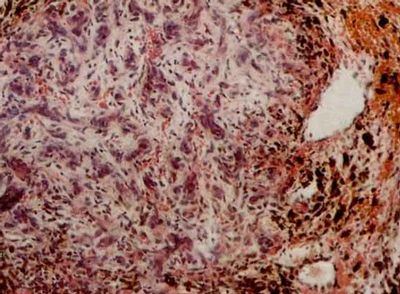

图注:aposis肉瘤 皮肤活组织检查 石蜡切片H-E染色 光镜(4×10)(10×10)(10×40)可见肿瘤组织中有许多新形成的血管,血管扩张,内皮细胞肿大突出于管腔内,红细胞外溢,含铁血黄素沉积。肿瘤由成纤维细胞、上皮样细胞淋巴细胞组成,并有大小不等、染色较深的圆形、椭圆形细胞。